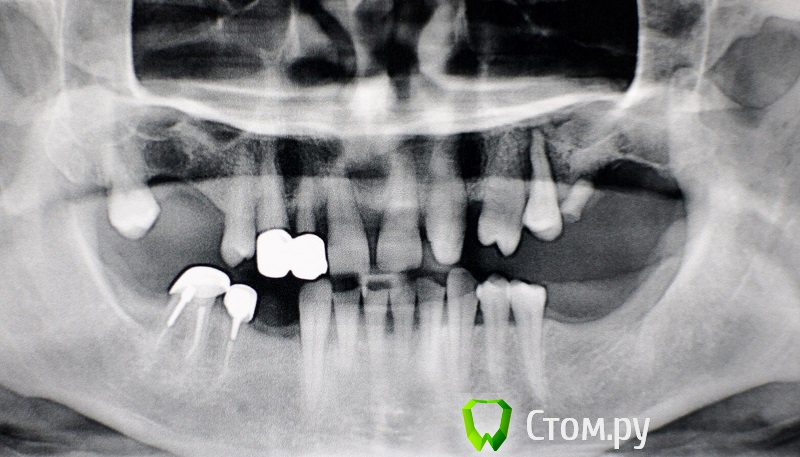

rin3225 Опубликовано 8 октября, 2014 Поделиться Опубликовано 8 октября, 2014 У пациента было желание сделать красивые зубы и улыбку!Проблема заключалась в массивной верхней челюсти , глубоком перекрытии и пациент не мог уйти без зубов! Отлив модели и выставив в центральную окклюзию было понятно, что без удаления всех зубов и поднятия прикуса с данной проблемой вопрос не решится. Обговорив все нюансы с пациентом,и получив согласие, было запланировано. заранее изготовлены акриловые протезы, предложено удаление всех зубов с одномоментной установкой имплантатов, внутриротавая сварка для первичной стабильности имплантатов и немедленная нагрузка 16 Ссылка на комментарий

rin3225 Опубликовано 8 октября, 2014 Автор Поделиться Опубликовано 8 октября, 2014 Я бы сделал фиксированную конструкцию с минимальным количеством опор и более рациональным их расположением. Я бы сделал фиксированную конструкцию с минимальным количеством опор и более рациональным их расположением.С двух сторон синус + удаление, первичная фиксация импантов 2/4 имплантата + прикус , какой прогноз? Ссылка на комментарий

Дмитрий Никитюк Опубликовано 8 октября, 2014 Поделиться Опубликовано 8 октября, 2014 С двух сторон синус + удаление, первичная фиксация импантов 2/4 имплантата + прикус , какой прогноз? Да, и нижний фронт оставил бы. Для синусов показаний не вижу. Но даже если бы их и нужно было делать, ограничился бы установкой 4-6 имплантатов, на которые одел бы 10-12 несъёмных зубов. Ссылка на комментарий